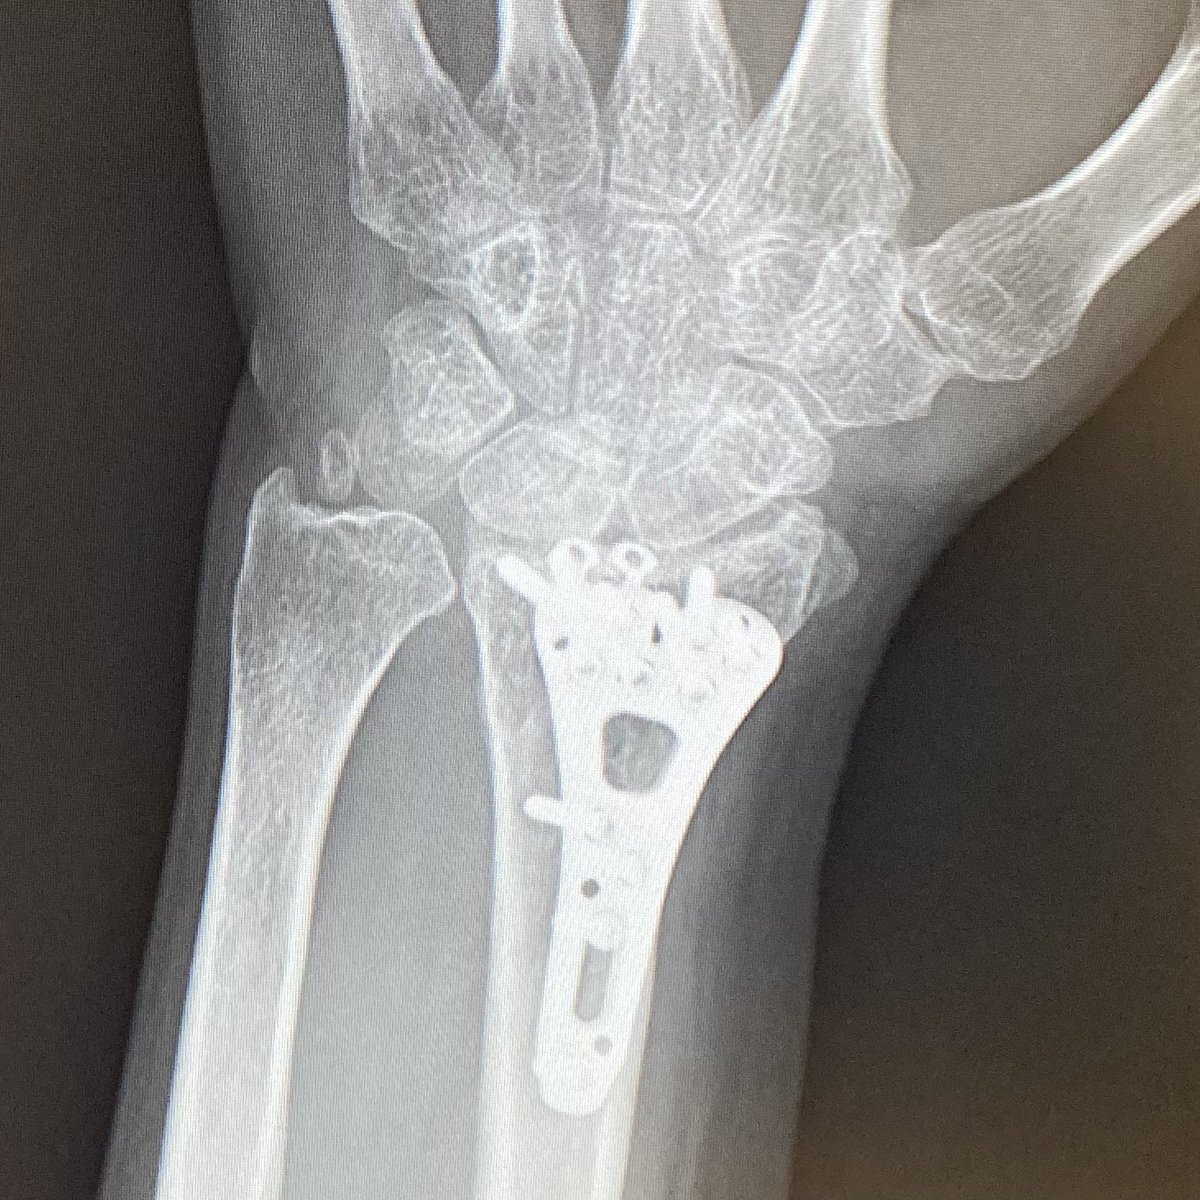

橈骨の抜釘手術(プレート除去)は来年1月になった。できれば年内にやりたかったな🥹 #橈骨遠位端骨折(粉砕) pic.x.com/oatzTfRtxU